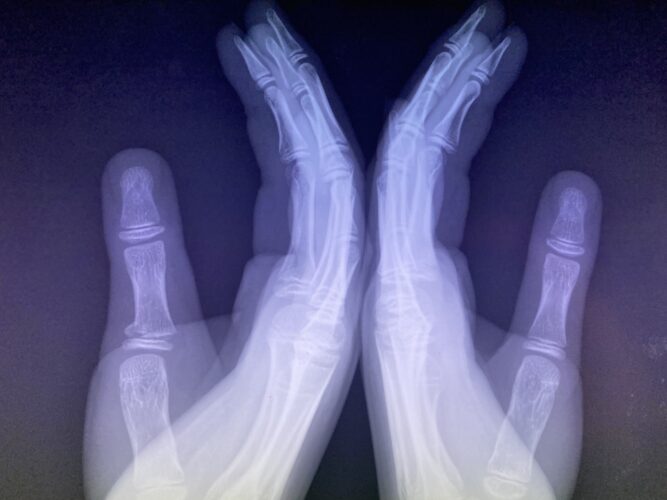

さわやか千葉県民プラザ(指骨骨折)